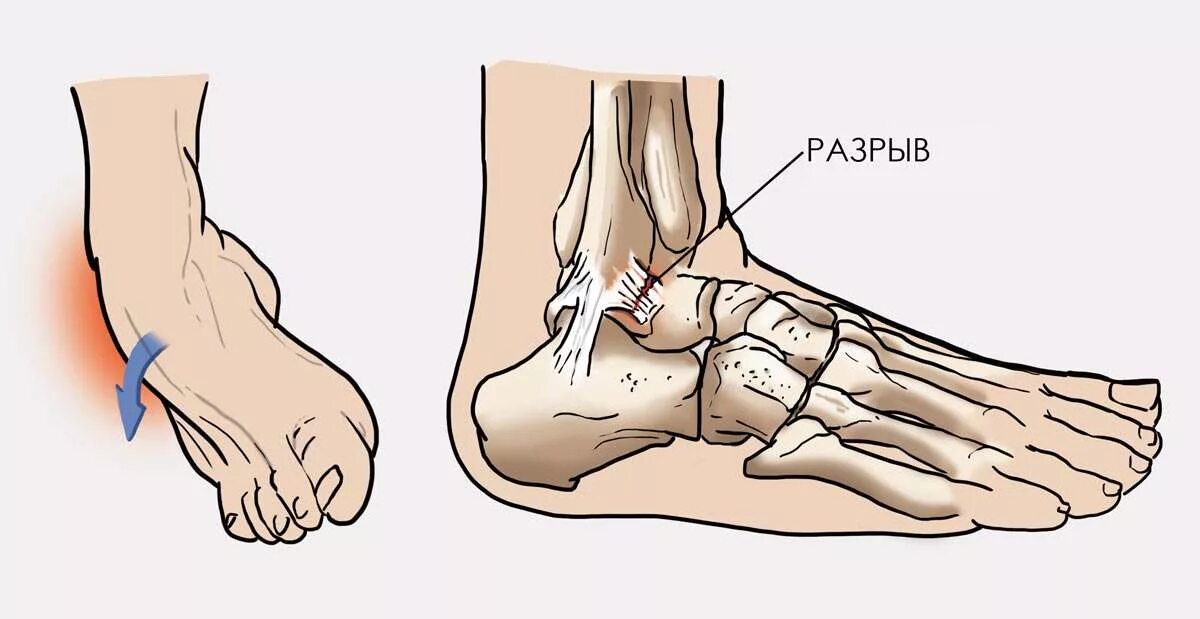

Вывих сустава стопы